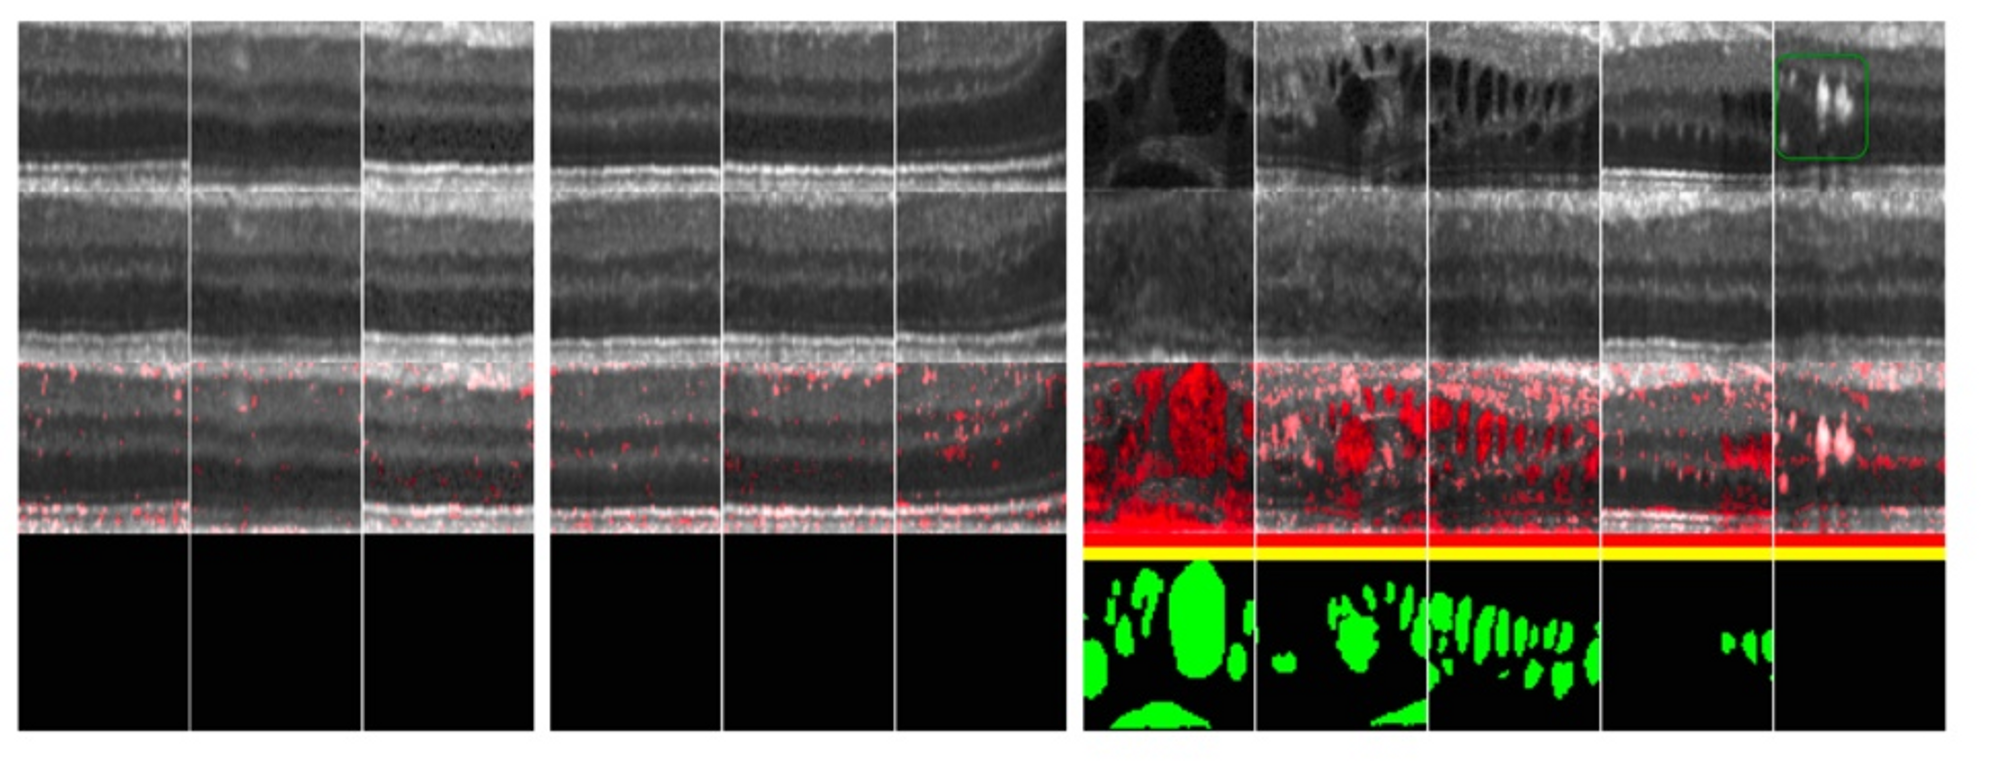

이렇게 학습이 끝난 후 정상/비정상 데이터를 model에 넣고 평가를 진행한다. 지표를 통해 평가하고, 오른쪽 빨간색 영역과 같은 model이 어느 부분을 보고 비정상 데이터로 구분했는지도 시각적으로 확인 가능하다.

아무튼 model은 DC GAN을 약간 변형시켜 각 convolution의 channel을 절반씩 줄인 것을 사용하였고, 행의 정보는 다음과 같다.

1행: 진짜 이미지

2행: G가 생성한 가짜 이미지

3행: residual 이미지

4행: 인간이 라벨링 한 비정상 영역

결과적으로 보면 해당 모델이 비정상 영역을 잘 포착한 모습을 볼 수 있다.